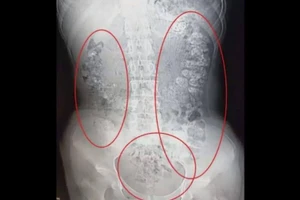

Táo bón nhiều ngày, phải nhập viện vì hạt trân châu trà sữa